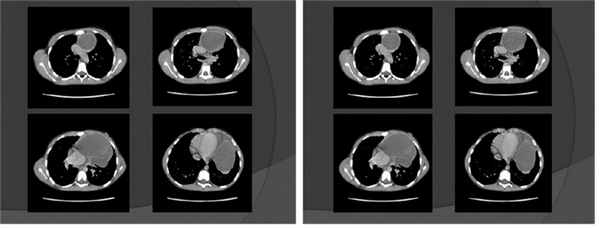

ЭКГ — синусовая аритмия с ЧСС 94 уд/мин (нормокардия). Диффузные изменения миокарда. УЗИ внутренних органов и почек без патологии. Рентгенография грудной клетки показала увеличение размеров сердца ( рис. 1 ).

Рис. 1. Рентгенограмма грудной клетки девочки Т., 9 лет. Иллюстрация В.Г. Молчанова, врача-рентгенолога ГАУЗ АО «Амурская областная детская клиническая больница»

ЭхоКГ — сердце смещено вправо образованием грудной клетки. Перегородки прослеживаются. Ускорение кровотока в легочной артерии, возможно, за счет сдавления извне. Выпот в полости перикарда, возможно, реактивный. Камеры сердца не увеличены. Сократительная способность левого желудочка в норме.

Заключение УЗИ: образование грудной клетки, исходящее из средостения? Левого легкого?

Проводилась дифференциальная диагностика с различными заболеваниями: новообразованиями средостения, легких и сердца, кистами легкого и перикарда, аневризмой аорты. Необходимо было также определить происхождение данной кисты, т. к. принято выделять истинные, или первичные, кисты средостения; кисты, образованные из органов и лимфатических сосудов; паразитарные (чаще всего эхинококковые) и, наконец, кисты, образованные из пограничных областей (например, менингеальные, т. е. из оболочек спинного мозга, и др.). После КТ диагноз был установлен, разрабатывалась тактика лечения.

КТ органов грудной клетки — картина кистозного образования средостения слева. Небольшой объем жидкости в плевральной полости слева и в перикарде ( рис. 2 ).

Рис. 2. Компьютерная томограмма грудной клетки девочки Т., 9 лет. Иллюстрация М.Ю. Петрова, заведующего отделением, врача-рентгенолога ГАУЗ АО «Амурская областная детская клиническая больница»